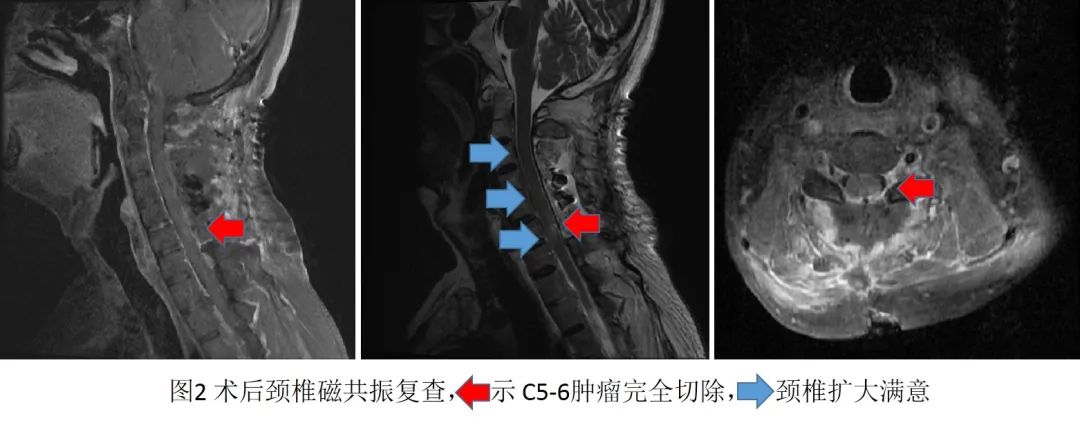

手术视野充分暴露后,王贵怀发现蔡先生体内的肿瘤与常见的脊髓肿瘤不同,病变一半嵌在脊髓内,另一半暴露在脊髓外,属于外生型的脊髓髓内肿瘤。结合多年的临床经验,肿瘤很有可能是良性病变,手术需要在保证神经功能的同时,尽量全切肿瘤。在显微镜高倍放大、超清视野下,王贵怀沿肿瘤周围胶质增生带,仔细剥离肿瘤,确保正常脊髓不受损伤,双极电凝灼烧后分块切除外生部分肿瘤,减轻脊髓压力;然后在显微镜下切除脊髓内肿瘤,实现镜下肿瘤全切除。手术同时为蔡先生进行了椎管扩大成形。术后病理检查证实,蔡先生罹患的是神经鞘瘤,这种脊髓髓内的类型发病率不足万分之一。在后续复查的影像中,肿瘤切除满意,颈椎管空间也得到了很好的扩大。